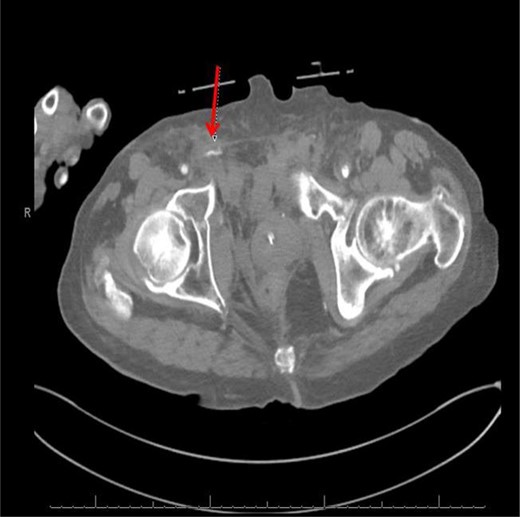

CT angiogram demonstrating successful embolization of AV fistula.

After resolution of the traumatic arteriovenous fistula (Fig. 2), a second blush from the right distal internal pudendal artery was identified and successfully treated with Gelfoam slurry. Subsequently, patient underwent exploratory laparotomy which revealed mesenteric and retroperitoneal hematomas. He also underwent craniotomy for evacuation of the subdural hematoma and open reduction internal fixation of the anterior and posterior pelvis. After discharge in fair condition to a subacute rehabilitation facility, patient developed a deep venous thrombosis managed by Coumadin.